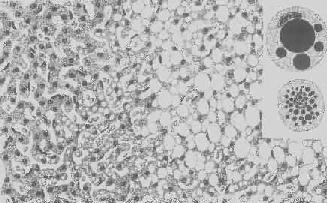

肝细胞脂肪变性

图1-18 肝细胞脂肪变性

肝细胞胞浆内出现大小不等的脂肪空泡;右上角为饿酸染色的脂肪细胞, 脂滴染成黑色

形态学:轻度肝脂肪变性时,肝肉眼观可无明显改变,或仅轻微黄染。如脂仿变性比较显著和广泛,则肝增大,色变黄,触之质如泥块并有油腻感。镜下,肝细胞内的脂肪空泡较小,起初多见于核的周围,以后变大,较密集散布于整个胞浆中,严重时可融合为一个大空泡,将细胞核挤向胞膜下,状似脂肪细胞(图1-18)。脂肪变性在肝小叶中的分布与其病因有一定的关系,例如肝淤血时,小叶中央区缺氧较重,故脂肪变性首先在此处发生。但长期淤血后,小叶中央区的肝细胞大多萎缩、变性或消失,于是小叶周边区肝细胞也因缺氧而发生脂肪变性。磷中毒时,肝细胞脂肪变性则主要发生于小叶周边区,这可能是由于此区肝细胞对磷中毒更为敏感的缘故。